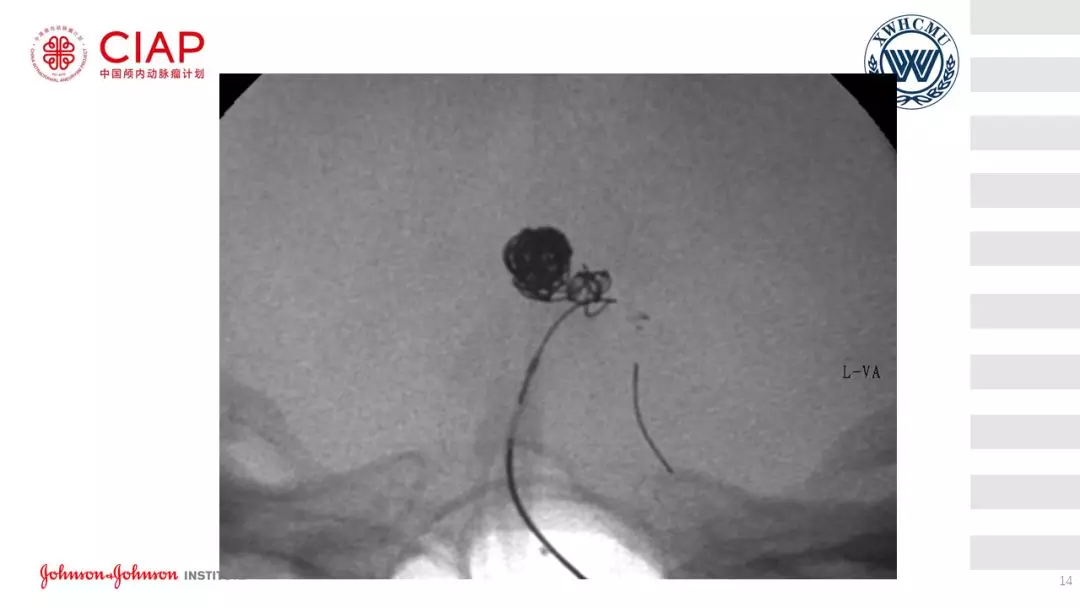

张鹏教授:不同辅助方法下栓塞动脉瘤弹簧圈的选择